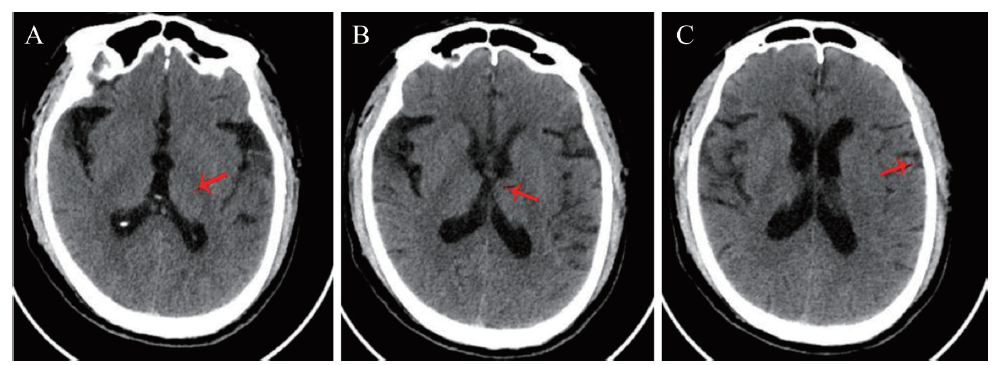

在患者入院24 h内完善相关检查。血常规:血红蛋白 155 g/L、红细胞 4.75×1012/L、白细胞 12.51×109/L、中性粒细胞0.78、血小板 189.00× 109/L。降钙素原、肝肾功能、输血前3项(获得性免疫缺陷综合征、丙型肝炎和梅毒)、抗血细胞抗体、抗核提取物抗体、免疫系列等均未见异常。脑脊液检查:腰椎穿刺测得压力190 mmH2O(1 mmH2O = 0.0098 kPa)。脑脊液:白细胞23.00×106/L,单个核细胞百分比 88.70%,多核细胞百分比11.30%;氯117.6 mmol/L,IgG 50.33 mg/L,总蛋白582.15 mg/L;脑脊液病原学检查未见明显异常。患者躁动不安,不能配合完成头颅MRI,遂立即实施头颅CT,可见左侧颞叶皮质肿胀(图1),头颅CT血管成像(CTA)未见颈部血管狭窄,头颅CTP可见左侧颞叶灌注较右侧增加(图2),排除急性脑梗死,不排除感染相关性疾病,初步考虑病毒性脑炎的可能。肥达反应+外斐反应、新型隐球菌荚膜多糖抗原检测(GXM,血清)均为(-)。动态脑电图:背景活动以7~8 Hz慢a波为主,右额颞区可见间隔0.8~2.0 s三相波、尖慢复合波呈周期性发放。重度异常脑电图(爆发-抑制)。脑脊液病原体二代测序(NGS)结果于入院后第3日回报,明确诊断为HSV-1感染所致的HSE。

图1 一例HSE患者头颅CT

注:可见左侧颞叶皮质肿胀,局部脑沟消失(红色箭头所示)。